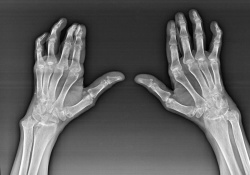

Эффективное медикаментозное лечение артроза кистей рук возможно только при наличии точной клинической картины. При диагностировании обязательно делаются рентгеновские снимки. Рентген позволяет обнаружить патологические изменения еще на ранней стадии.

ДИАГНОСТИКА АРТРОЗА КИСТИ Врач проводит визуальный осмотр, оценивая наличие отека, покраснения, деформаций, уменьшения подвижности и болезненности в кистевых суставах. Рентгенография кисти. Данный метод позволяет увидеть изменения в структуре костей и суставов, определить степень развития артроза.